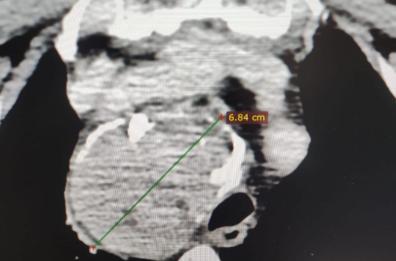

Al Policlinico di Bari effettuato per la prima volta un trattamento di radioembolizzazione epatica